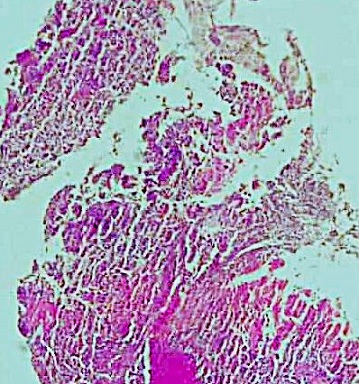

Histological analysis of the main tumor revealed a poorly differentiated tubular adenocarcinoma, grade III. The tumor was classified as pT3. There was no perforation, nor lymphatic, venous, or perineural invasion (Image 4). All lymph nodes were free of metastasis.

Poorly differentiated, grade III tubular adenocarcinoma of the stomach Picture 4: Poorly differentiated, grade III tubular adenocarcinoma of the stomach

A second tumor, located at a distance from the adenocarcinoma within the antrum, was incidentally identified. It was a well-differentiated neuroendocrine tumor measuring 1.8 mm, grade 1, confined to the mucosa and classified as pT1. Immunohistochemical staining for synaptophysin and chromogranin was positive. The mitotic index was 0/10 HPF, with a Ki-67 index below 1%. No alpha-fetoprotein staining was observed in this second tumor.